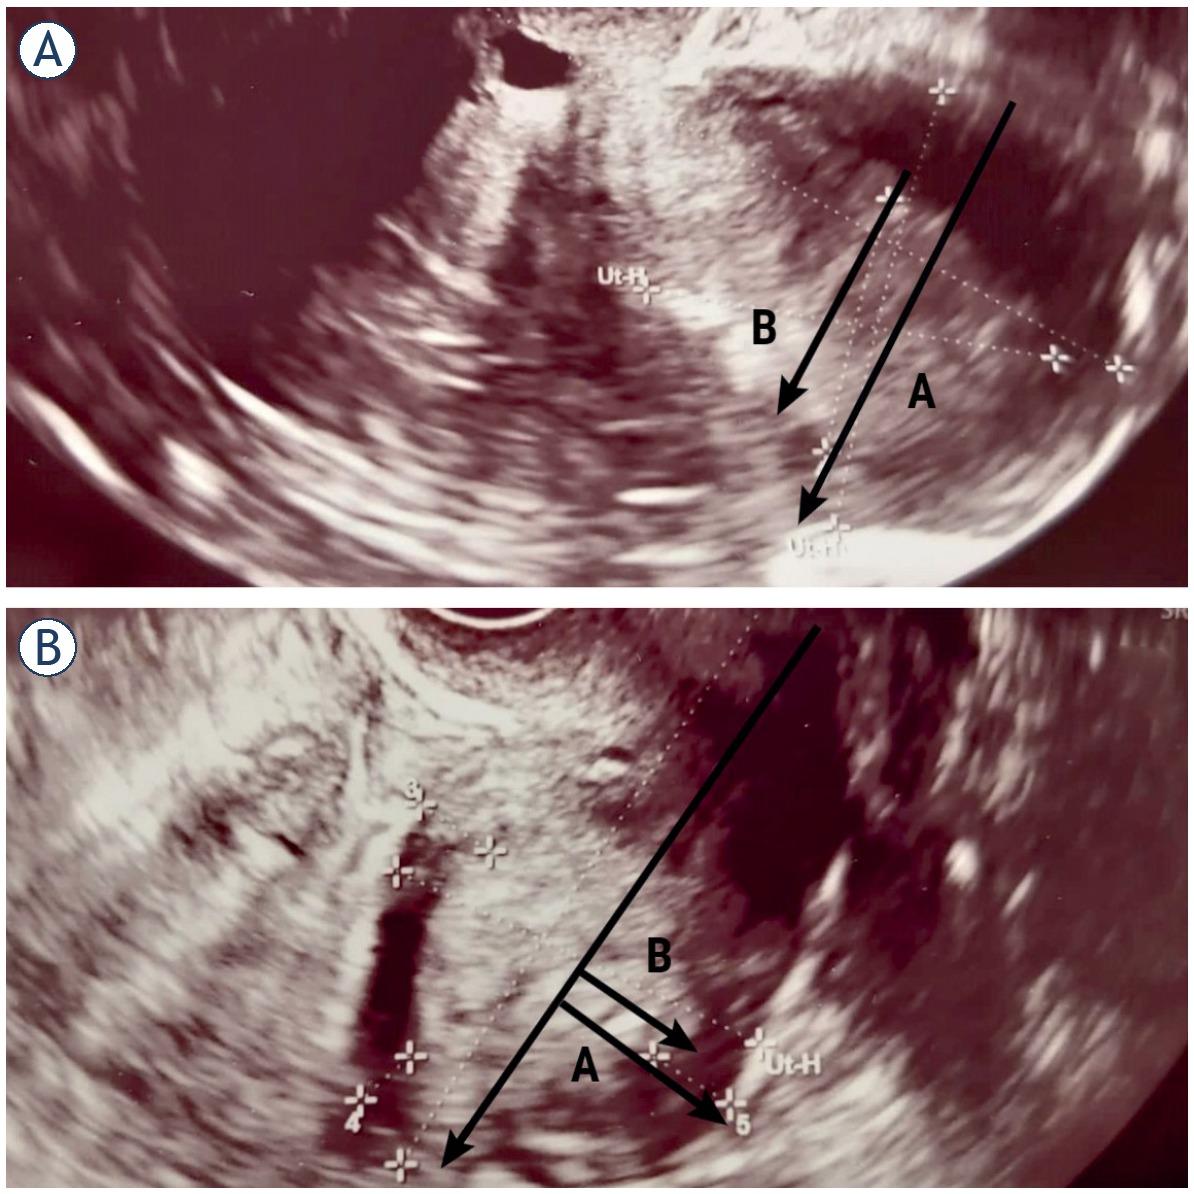

Depth of MI was measured as the ratio between the maximum AP diameter of the endometrial tumor (B) and the uterine AP diameter (A) in sagittal plane, with B/A > 50% indicating deep MI introduced by Karlsson et al. (Figure 1A,Figure 2A).2,5 In other objective method, investigated by Gordon et al., depth of MI was measured as the ratio of the distance between the maximum tumor depth (B) and the total myometrial thickness (A) in sagittal plane, with B/A > 50% indicating deep MI (Figure 1B,Figure 2B).2,5

Assessment of myometrial invasion in patients with transvaginal ultrasonography (TVUS). Stage IB endometrial cancer in a 78-year-old postmenopausal woman, correctly diagnosed by TVUS and MRI. Karlsson’s method indicating infiltration of deep muscle (58%) (A). Stage IB endometrial cancer in an 83-year-old postmenopausal woman. Gordon’s method indicating infiltration of deep muscle (73%) (B).